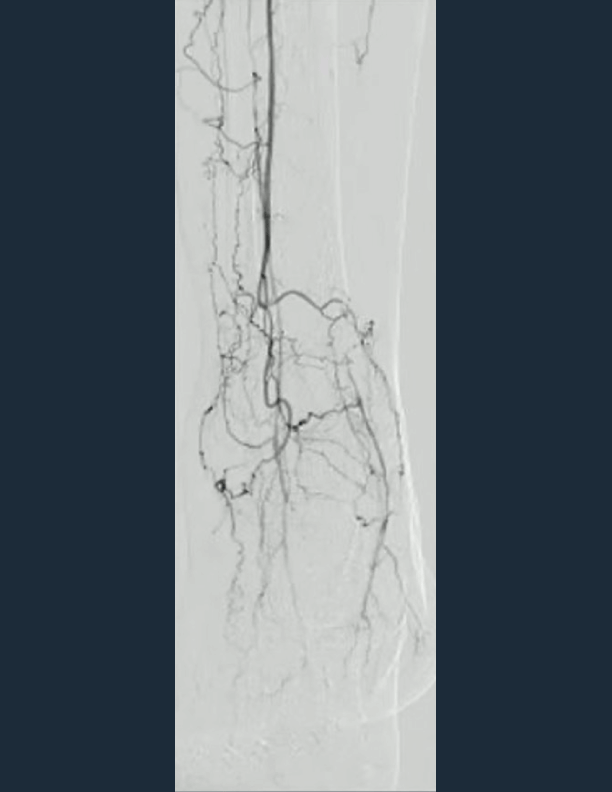

• Final angio shows direct flow to metatarsal arteries

Final angio shows direct flow to metatarsal arteries and palpable pulses with resolution of rest pain. 5th toe amputation was completed post procedure with triphasic signals in foot following DUS assessment